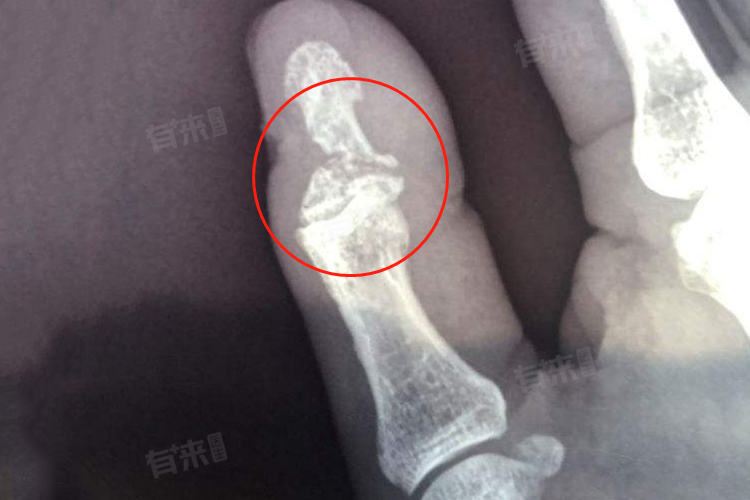

大拇指骨折恢复时间一般在3-12个月时间,但具体时间因骨折严重程度、治疗方法以及患者自身体质等因素而异。

- 但如果大拇指骨折伴有明显移位,甚至出现骨擦音、骨擦感等异常畸形活动,或者损伤到周围的血管、神经等组织,可能需要通过手术进行治疗。手术可能包括切开复位内固定等步骤,达到解剖复位效果。手术后恢复时间相对较长,因为需要等待骨折部位愈合和周围组织修复。